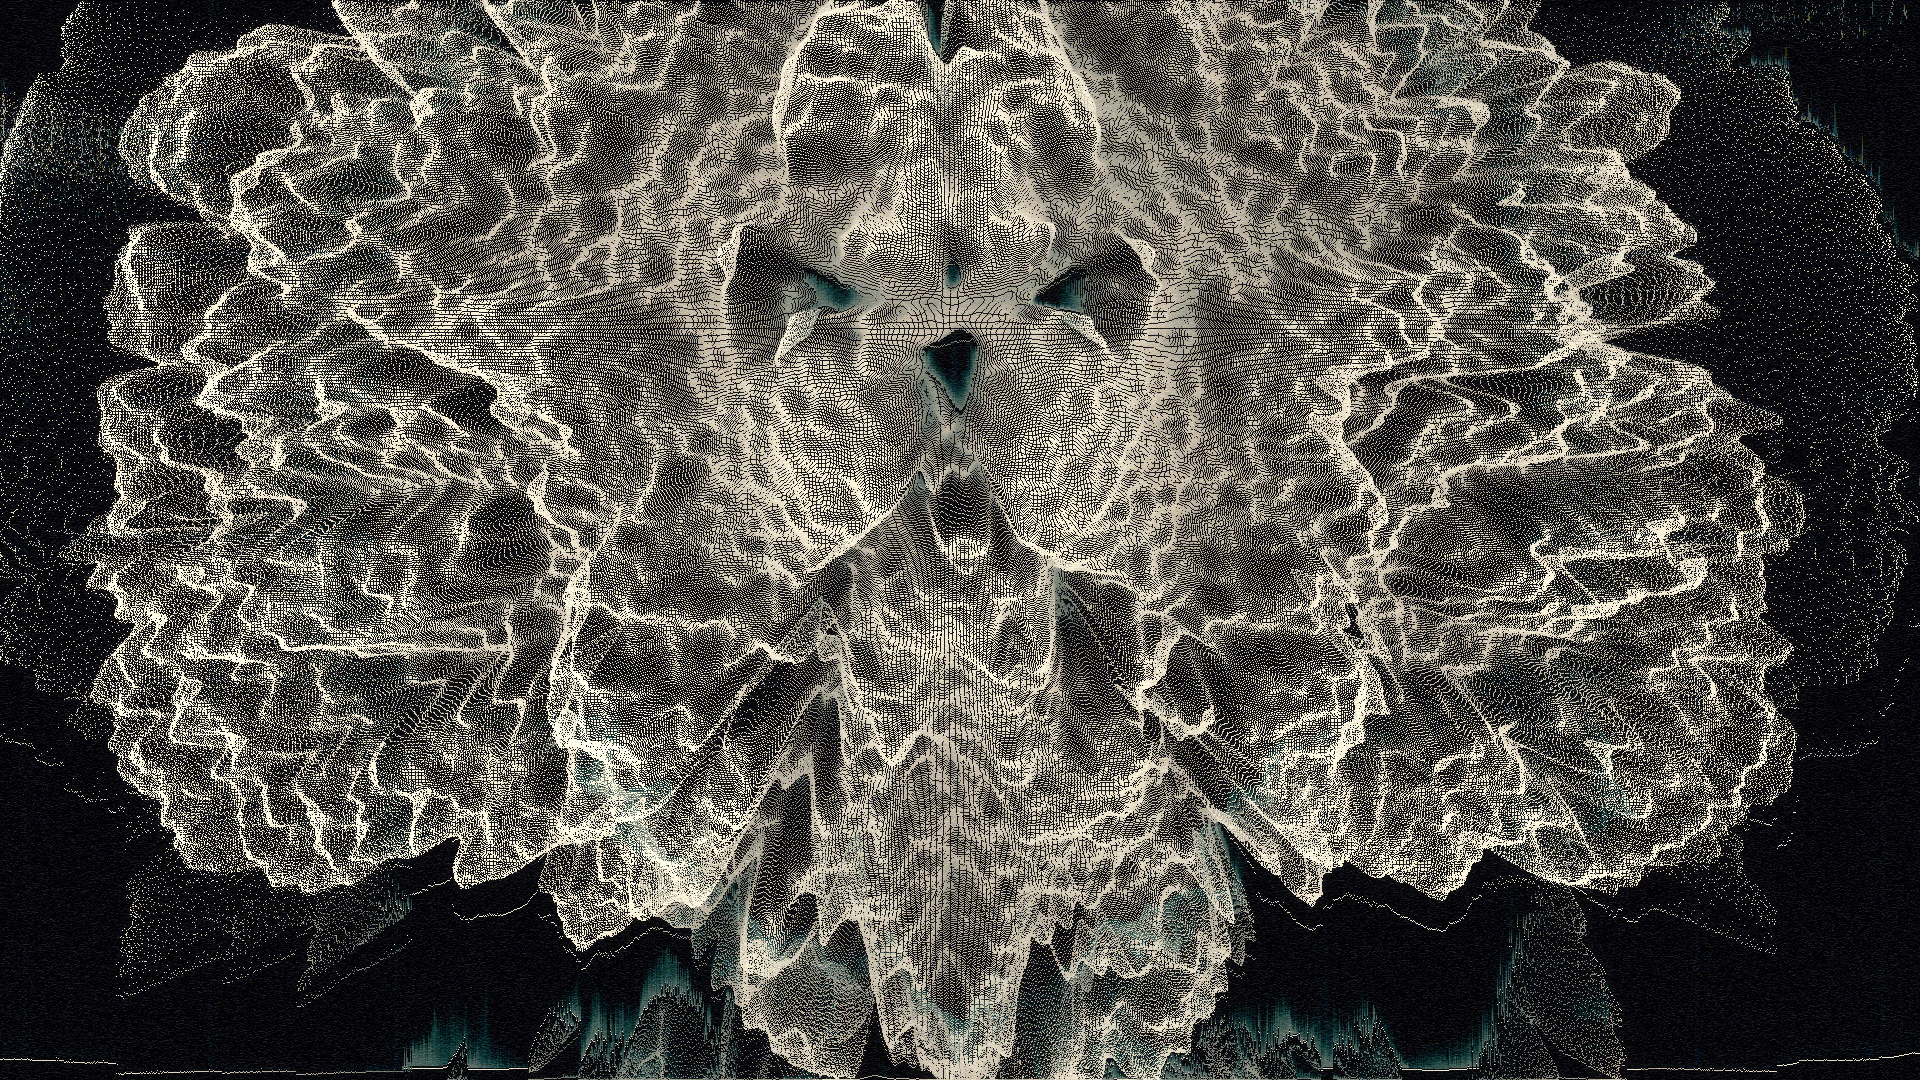

I recently developed style frames and animations for a television commercial. The main topic of the ad was to reflect Alzheimer's disease and what happened in the patient's brain.